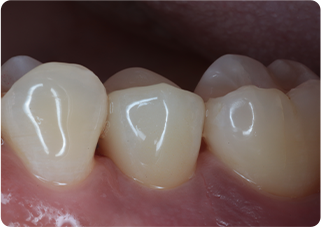

矯正的挺出・歯冠長延長術・セラミッククラウン症例②

術前

MTM、歯冠長延長後

術後

| 主訴 | むし歯の歯を抜きたくない |

|---|---|

| 治療期間/回数 | 5ヵ月、10回 |

| 価格(税込) | 154,000円(税込) |

| リスク・副作用 | セラミックの破損・脱離が生じる場合がある |

| ポイント | 通常だと抜歯と診断されるが、局所矯正と外科処置を行い、歯根を持ち上げることで、被せ物が可能になった。歯根を持ち上げたことにより長期的に安定した被せ物が可能になる。 |